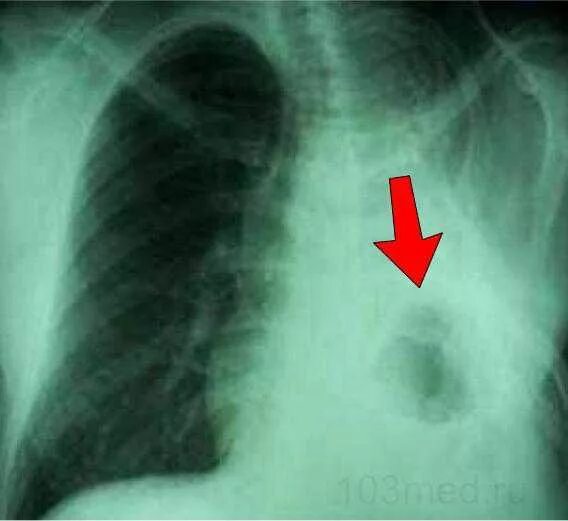

Пневмосклероз рентгенограмма